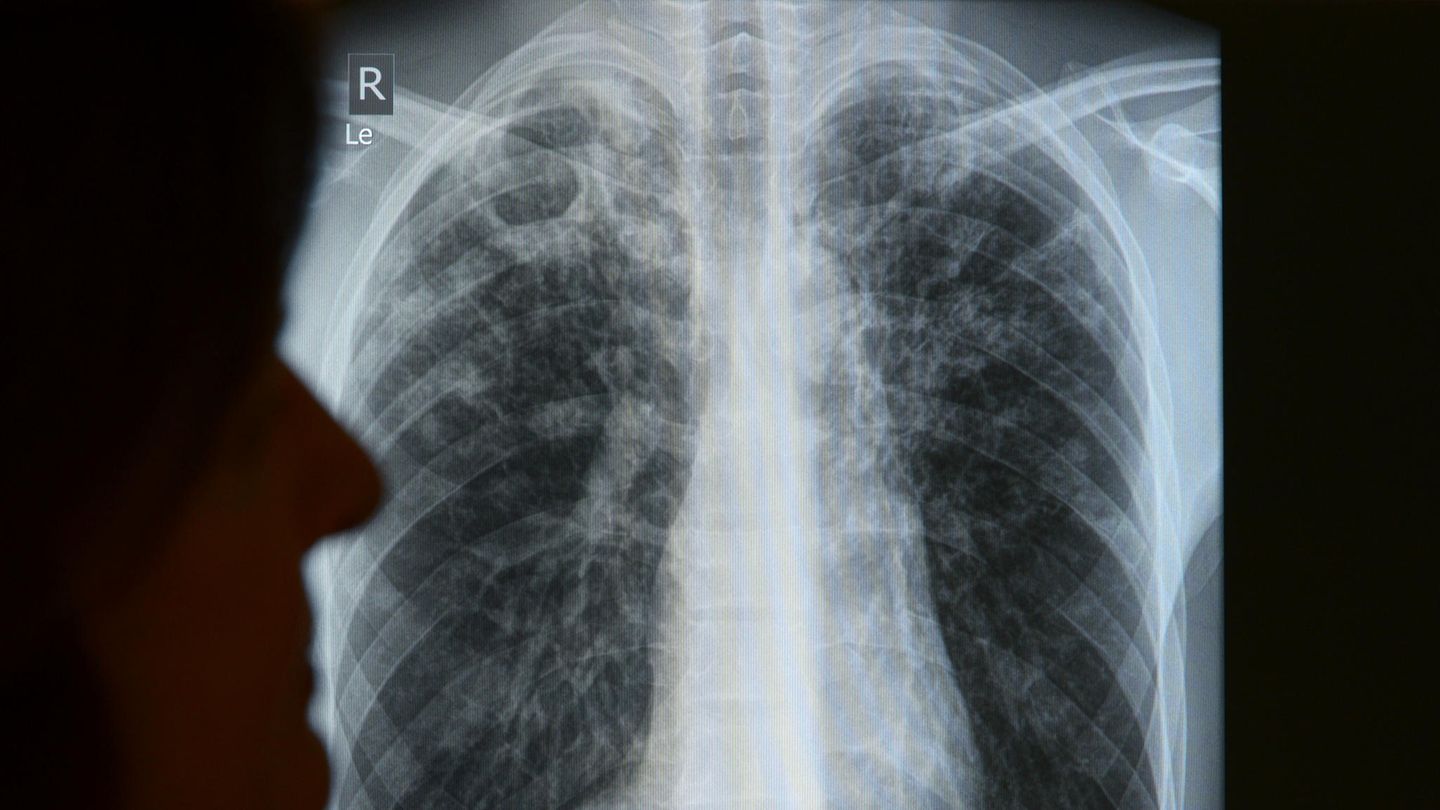

"Tuberkulose kommt in Deutschland vor. Aber eben nicht so häufig, dass jeder Arzt regelmäßig eine sieht", sagt Lena Fiebig. Deswegen denkt auch nicht jeder Mediziner bei längerem Husten, schwindenden Kilos und Nachtschweiß sofort an TBC - und einen Röntgencheck. Damit lassen sich häufig die typischen Veränderungen im oberen Teil der Lunge erkennen. Tuberkulose kann aber auch andere Organe befallen. Dann wird die Diagnose aufwendiger.